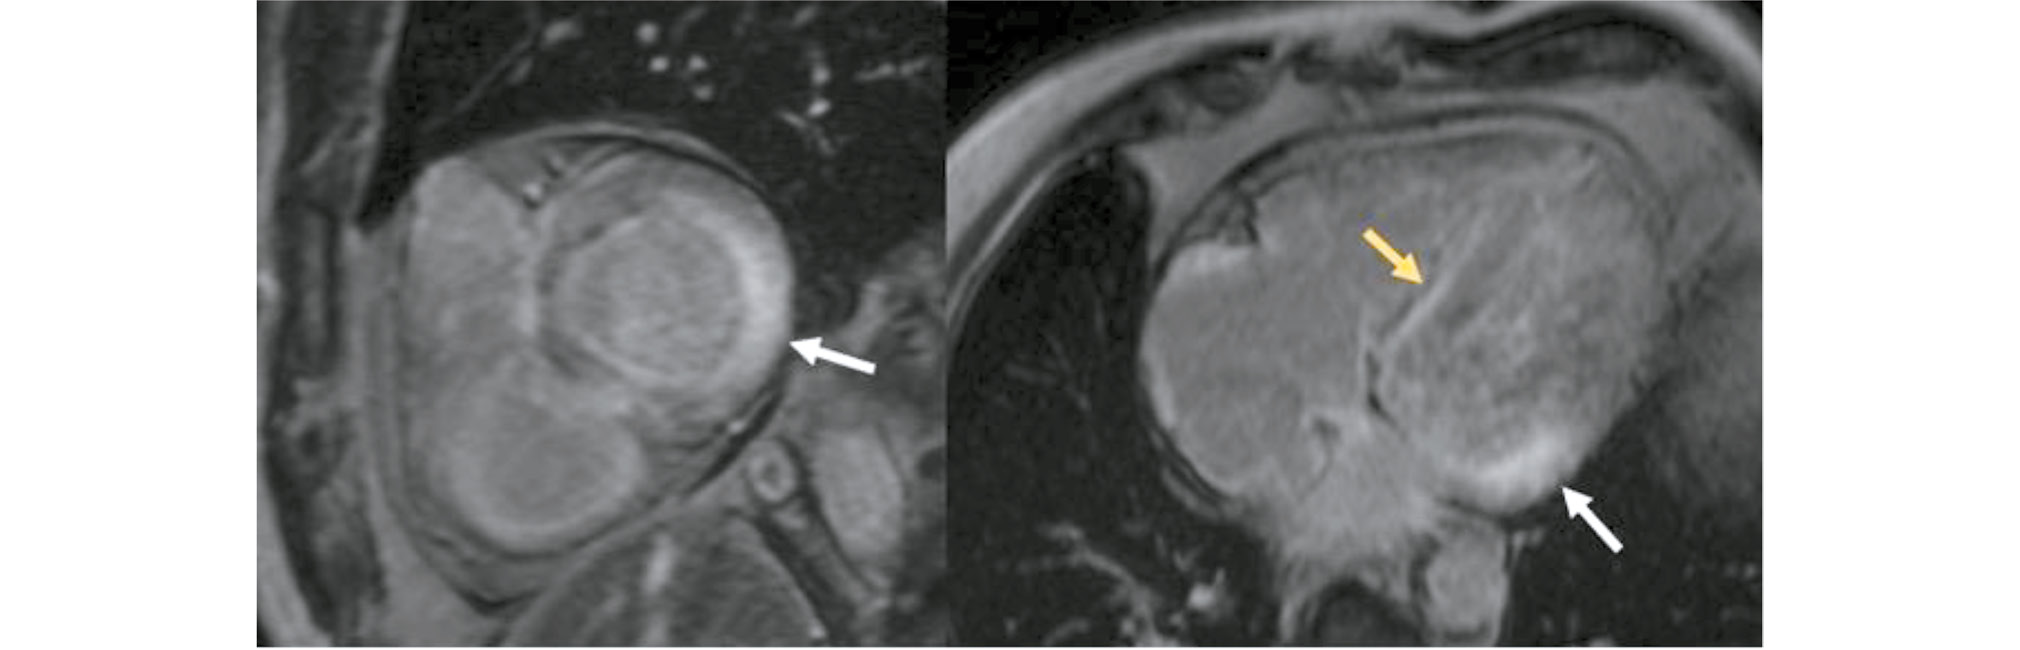

The analysis of contrast uptake distribution by cardiac segments revealed transmural LGE in Group 2 at the basal and middle levels (inferolateral segments, Fig. 4) (p < 0.05). Group 1 showed subendocardial LGE at the middle level (antero- and inferolateral segments, Fig. 5) (p < 0.05). The other segments showed no specific contrast uptake patterns (p > 0.05) (Table 3). The circular contrast uptake rates were not significantly different.

Fig. 5. Time-delayed contrast-enhanced cardiac magnetic resonance imaging scans in light-chain amyloidosis. Subendocardial contrast uptake at the basal and middle levels (inferolateral segments) of the left ventricular myocardium (white arrows).